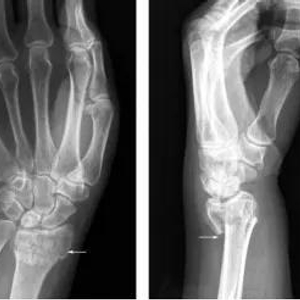

X线能清楚地拍出骨性结构(下图中白色轮廓清晰部分)但却不能清晰地分辨出软组织结构(边缘白色模糊部分)。因此,在常规摄片排除骨折表现后,患者通常会把受伤局部的肿胀、疼痛及运动障碍等不适,统称为“伤筋”,医学上则称为“软组织损伤”。

图1 手部X线片(白色部位为骨骼,边缘白色模糊部分为软组织)图片来源:X线读片指南——王书轩、范国光主编